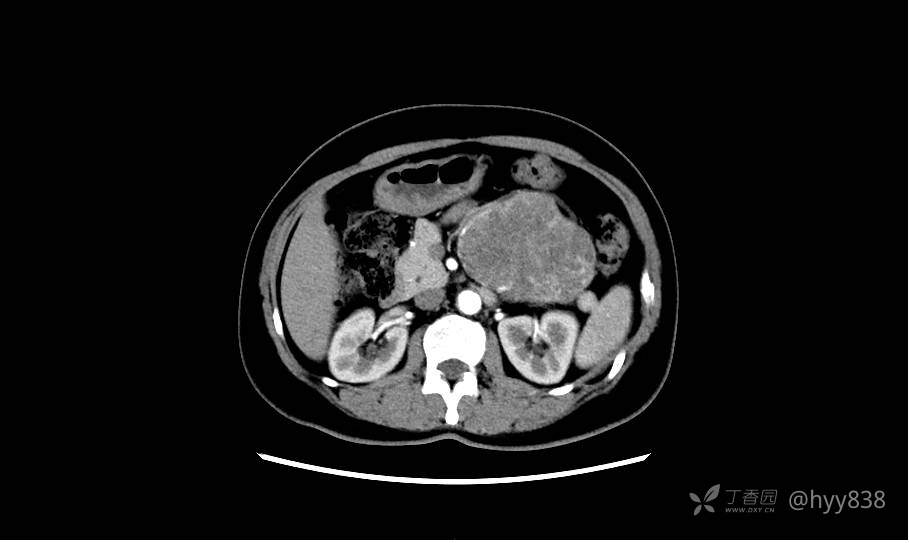

胰腺增强动脉期

静脉期(机器故障---延迟期了)